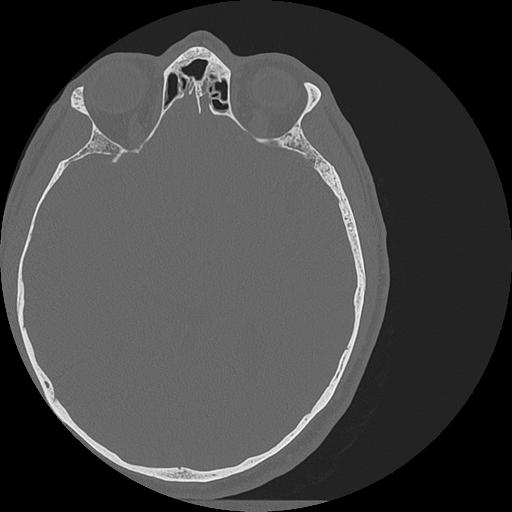

7 HUESO,,Vol,0.5,HUESO,,